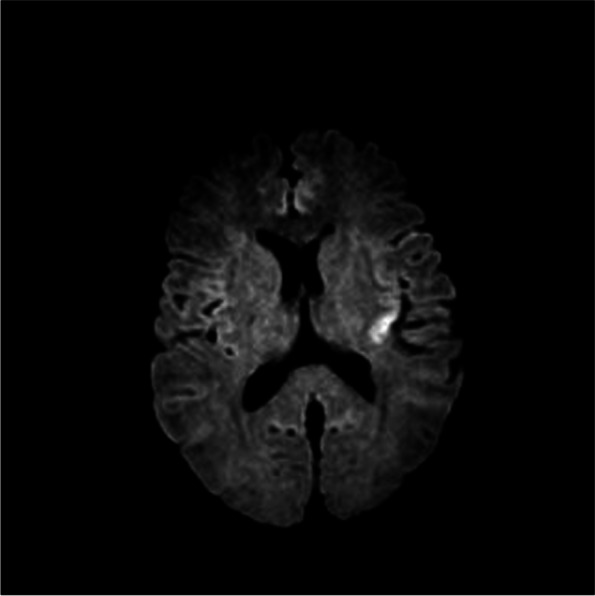

二甲亚砜致多发性骨髓瘤癫痫1例。

A case of dimethyl sulfoxide-induced seizure in multiple myeloma.